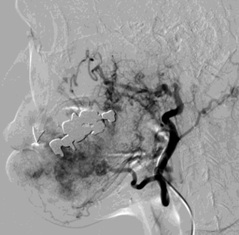

颈外动脉造影 |

面动脉造影 |

NBCA:碘油=1:6 |

栓塞后 |